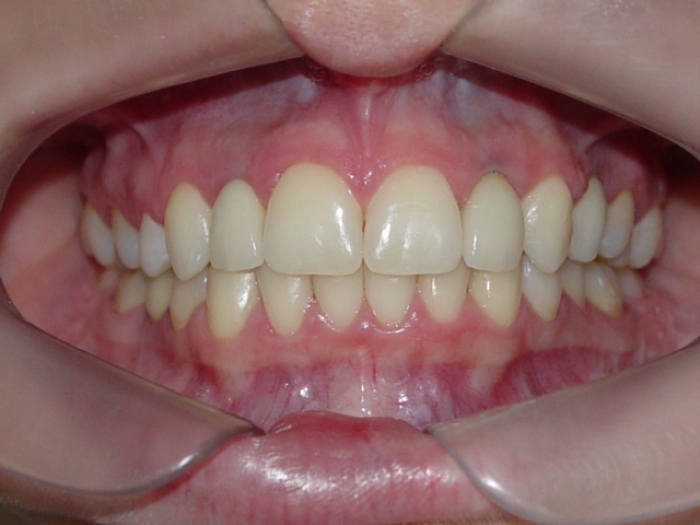

Imagem inicial